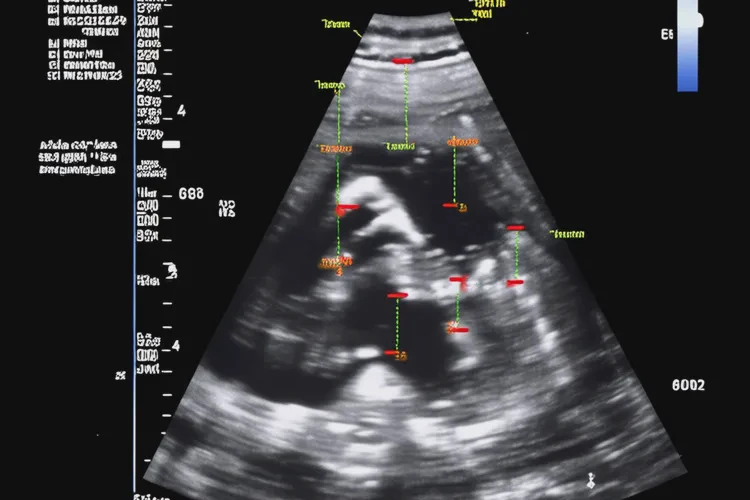

胎兒心率是評(píng)估胎兒宮內(nèi)健康狀況的重要指標(biāo)之一。在正常情況下,懷孕12周后可通過(guò)超聲多普勒技術(shù)檢測(cè)到胎心,此時(shí)胎心率通常在110-160次/分鐘之間。胎心率低于110次/分鐘被定義為胎心過(guò)緩,而86次/分鐘已顯著低于正常范圍,屬于嚴(yán)重胎心過(guò)緩,需引起高度重視。

- 重復(fù)超聲檢查:由專(zhuān)業(yè)醫(yī)師使用多普勒超聲或彩色多普勒血流顯像(CDFI)確認(rèn)真實(shí)胎心率,并評(píng)估胎兒心臟結(jié)構(gòu)、胎動(dòng)、羊水量及臍血流。